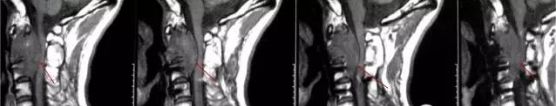

病情简介:男性,40岁。2008年12月手术,病理:脊索瘤。术后放疗,总量4320cGY,因难以避开受压迫的脊髓,剂量无法继续增加,治疗终止。

治疗一年后复查,肿瘤明显缩小,受压脊髓形态恢复正常,两年后复查,肿瘤未见进展,效果理想,无副作用出现。

质子治疗前影像:脊髓受压变形

治疗后图像:肿瘤明显缩小,脊髓形态恢复正常

10年后随访,未见复发。